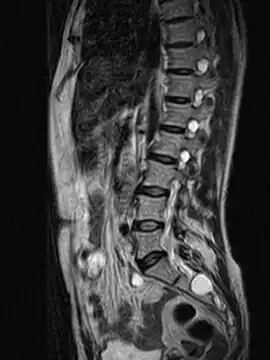

MRI

MRI, or Magnetic Resonance Imaging, is considered the imaging study of choice in identifying Tarlov cysts. MRI provides better resolution of tissue density, absence of bone interference, multiplanar capabilities, and is noninvasive. Plain films may show bony erosion of the spinal canal or of the sacral foramina. On MRI pictures, the signal is the same as the CSF one.